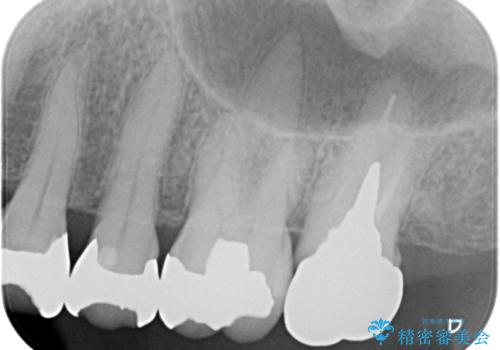

- 被せものに穴が開いたとのことで来院された患者様です。被せものをやり替えることになったので、かみ合わせが強い方のでPGAクラウンをご提案しましたが患者様の強いご希望によりオールセラミッククラウンによる補綴治療を行っていくことになりました。

拡大鏡視野下で、金属の被せもの、虫歯の除去を行い、オールセラミッククラウンに適した形に整えました。

患者様のご希望により、根管治療、土台のやり替えは行っていません。